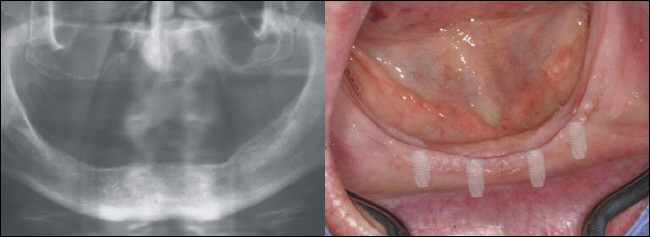

Einheilung

Bei der Variante der Spätversorgung heilen die Implantate im Unterkiefer zwischen zwei bis drei Monaten in den Kieferknochen unbelastet ein, das heiß es werden noch keine Kaukräfte in den Knochen weitergeleitet. |